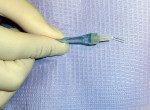

The author suggests that the clinician snap the handpiece off to make it shorter. This allows easier access to the injection site on the maxillary, but it allows easier access especially on the mandibular teeth (Figure 1). While keeping the STA System machine in the STA mode, locate the injection sites. The disto–buccal line angle and then the mesial–buccal line angle are the injection sites on the maxillary teeth. The injection sites for the mandibular teeth are the distal–lingual line angle and then the mesial–lingual line angle, finishing with the buccal furcation on the molars. The clinician should always start with the distal site on all teeth. Bend the needle approximately 10º to 15º toward the bevel and insert the needle into the PDL with the bevel of the needle placed toward the tooth. Keep this position during the entire injection. Set the machine on cruise control and administer the anesthetic at the control flow rate. Move the needle deeper into the sulcus until resistance is met. Hold the STA System handpiece in place for 15 seconds while listening for the audible tones and light signals that indicate the needle is in the PDL space. When the correct injection site has been reached, administer one quarter of a carpule of 4% articaine (1:200,000). After the correct amount of anesthesia has been injected, wait 6 seconds and slowly back out the needle. Complete the injection sequence. Once the sequence is completed, the tooth should be anesthetized pulpally and on the buccal and lingual.